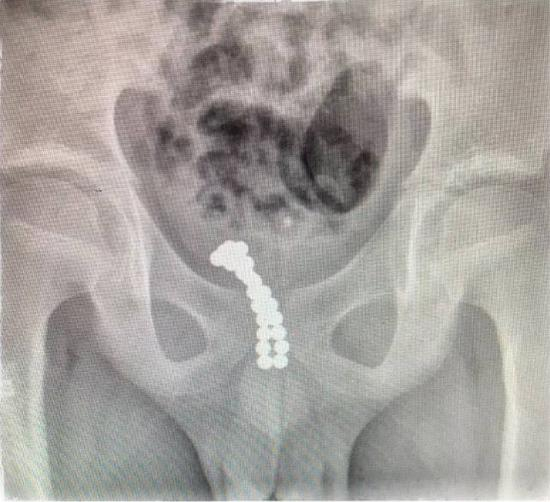

了解情况后,医生安排皮皮做了X光检查。检查结果让医生大吃一惊——皮皮的体内有20多颗珠子一样的异物吸附在一起,其中十几颗进入了膀胱,另外有几颗卡在尿道口。随后,皮皮被转到温医大附二院小儿外科进一步治疗。

王永飚介绍,切开膀胱后,他看见里面有10多颗磁珠,另外有七八颗珠子牢牢地卡在皮皮的后尿道处。一般11岁孩子的尿道直径在5毫米左右,而珠子直径为3毫米,进入体内之后两个一组吸在一起,也就是说6毫米的异物卡在了尿道处,引起了尿道的肿痛、流血。最终,医生共取出了26颗。